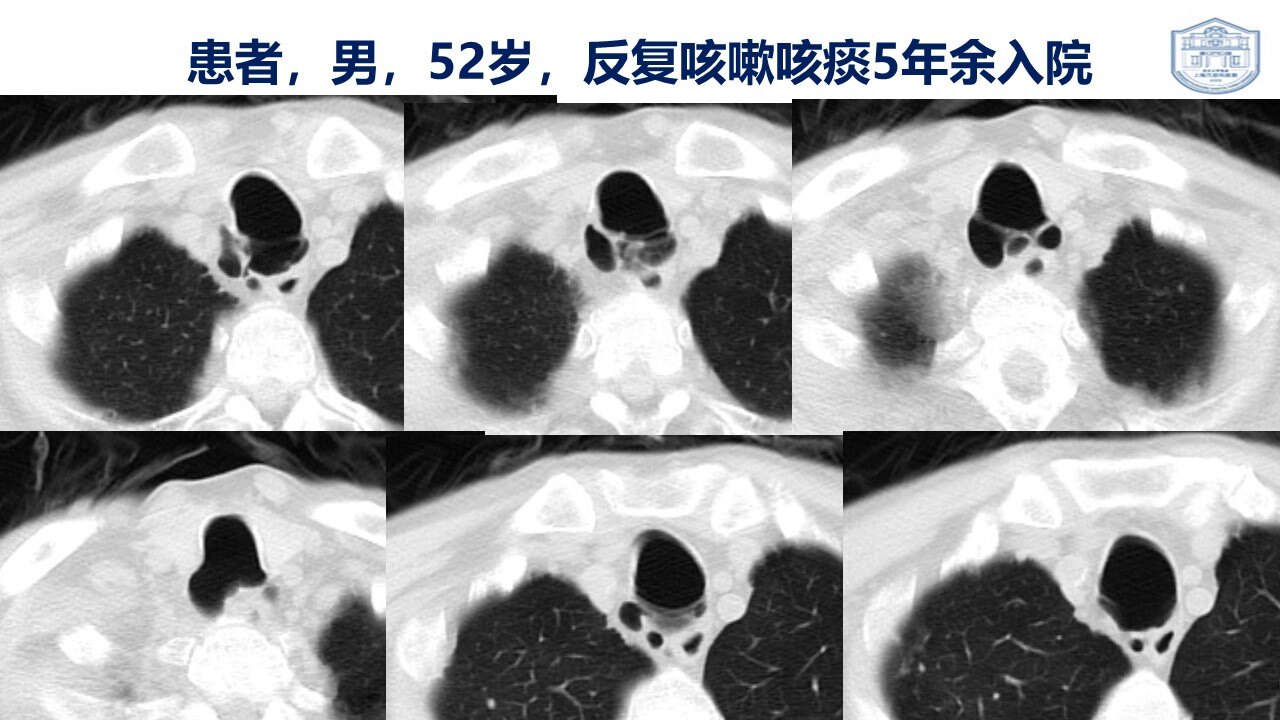

气管,支气管憩室